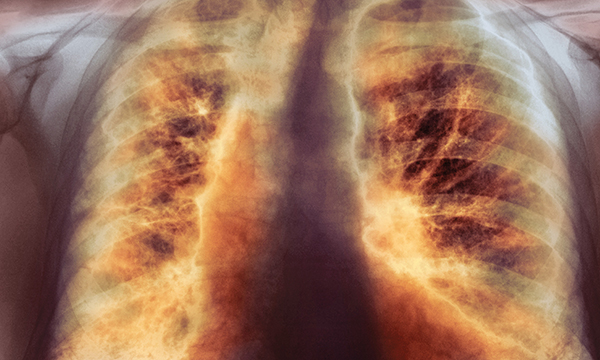

This is a summary of the peer-reviewed article: Abdominal X-rays in children: indications, proced